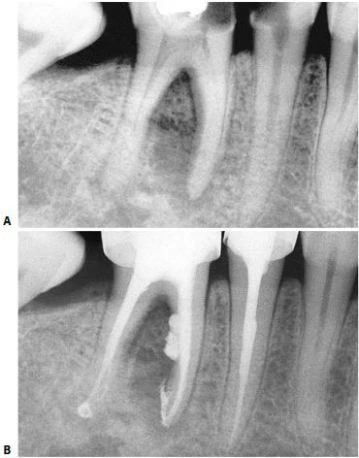

Mở xoang tủy nhìn chung răng cối lớn một hàm dưới có 2 chân phân biệt hình tròn hay thường là elip, ống tủy ở chân xa (hình 11.106) và 2 ống tủy ở chân răng gần. Trong 90% trường hợp chúng đổ ra 2 lỗ chóp khác nhau (hình 11.107) và 10% chúng hợp lại và đổ ra 1 lỗ chóp (hình 11.108).

Hình 11.106. Xoang tủy ở 1 R36: miệng củanhững ống tủy gần khá tròn còn ở ống tủy xa thì thường có hình elip.

Hình 11.107. Các ống gần của răng cối lớn một dưới có những lỗ chóp phân biệt. Chú ý rằng có nhiều ống tủy phụ ở 1/3 chóp (Courtsey of Dr. M. Scianamblo).

Hình 11.108. Các ống gần của răng cối lớn dưới hợp chung lại rồi đổ ra ở cùng một lỗ chóp. Có thể thấy nhiều ống tủy phụ ở chân xa.